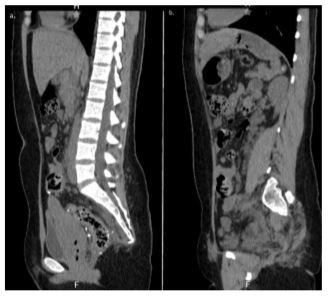

In 2017, she presented with grade I hemorrhoids, and a colonoscopy revealed angiodysplasia in the rectum associated with a hemangioma. Argon plasma coagulation was carried out, with a satisfactory outcome. After one month, a new colonoscopy showed ectasia in the rectum with irregular mucosa and changes likely associated with a hemangioma. An abdominal MRI scan in the sagittal plane with contrast was performed, demonstrating hyperintensities in the colorectal wall compatible with angioembolization material, in the context of a history of hemangioma. The lumbar spine showed loss of lordosis, while the pelvic region exhibited heterogeneous findings consistent with sequelae of previously embolized arteriovenous malformations (Figures 1a and 1b).

Figure 1. Abdominal MRI scan in the sagittal plane with contrast. 1a) Colorectal wall showing angioembolizations and lumbar spine with loss of lordosis. 1b) Heterogeneous findings in the pelvic region consistent with sequelae of arteriovenous malformations.